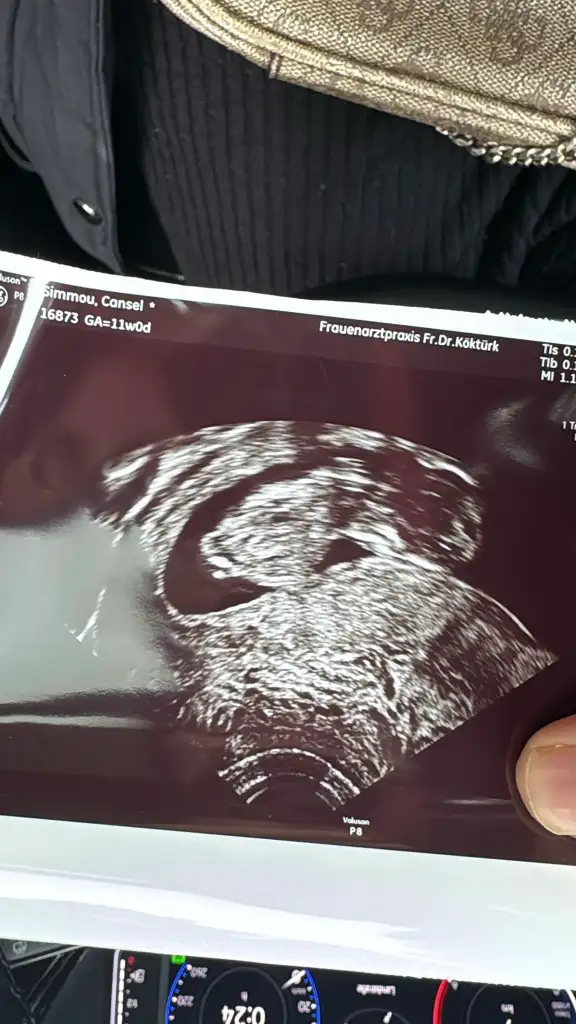

Ramzi teorisine göre tahmin yapalım

Merhaba acaba banada tahminde bulunur musunuz:)abdominal(karından)çekildi

8+3 karından ultrasonla çekildi cinsiyet tahmini yapabilecek var mı